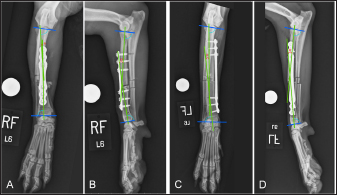

Fig. 5. Orthogonal radiographic images of plated radii illustrating trends in frontal and sagittal plane angulation following cranial (A–B) and medial (C–D) plating. Proximal and distal joint reference lines were drawn and joint reference angles were transferred from the intact radii to the plated radii to establish proximal and distal anatomic axes to determine frontal and sagittal plane malalignment. In the cranial plated radius (A–B) there is slight (1°) valgus angulation (A) and decreased (by 7.7° to 5.2°) procurvatum (B), following plating. In the medial plated radius (C–D) there is slight (3.9°) varus angulation (C) and decreased (by 4.4° to 6.7°) procurvatum (D), following plating.

Six plated radii in each plating group had some degree of valgus and four plated radii in each plating group had some degree of varus. Frontal plane alignment of cranially plated radii ranged from 11.1° valgus to 3.5° varus. Frontal plane alignment of medially plated radii ranged from 4° valgus to 12.8° varus. Post-procedural frontal alignment (mean ± SEM: 1.8° ± 1.5° valgus and 1.2° ± 1.6° varus in the cranial and medial plating groups, respectively) did not differ between plating groups (p =0.10). Five radii in the cranial plating group had decreased procurvatum and five had increased procurvatum. Seven radii in the medial plating group had decreased procurvatum while three had increased procurvatum (Fig. 5). Sagittal plane alignment of cranially plated radii ranged from 3.0° to 18.2° of procurvatum. Medially plated radii had 5.2° to 21.4° of procurvatum. Post-procedural sagittal plane alignment (mean ± SEM: 11.5° ± 1.8° and 12.0° ± 1.6° in the cranial and medial plating groups, respectively) did not differ between plating groups (p =0.81). Procurvatum was decreased in both plating groups (mean ± SEM: −2.1° ± 1.5° and −1.7° ± 1.3° in the cranial and medial plating groups, respectively) and there was no difference in the magnitude of change in procurvatum between plating groups (p =0.82). Post-procedural radial length ranged from 117.6 to 171.6 mm in cranially plated radii and from 117.9 to 173.8 in medially plated radii. The post-procedural radial length of cranially plated radii was decreased relative to the intact radii (mean difference ± SEM: −1.06 ± 0.71 mm), while the radial length of medially plated radii was increased relative to the intact radii (mean difference ± SEM: 1.11 ± 0.54 mm). The post-procedural radial length was significantly different between plating groups (p =0.004) along with the change in radial length, compared to intact radii, between plating groups (p =0.002). “Near-anatomic” frontal plane alignment was obtained in eight cranial and nine medial-plated radii. “Near-anatomic” sagittal plane alignment was obtained in six cranial and seven medial-plated radii. Post-procedural radii were considered to have “acceptable” frontal plane alignment in one cranially plated radius. Post-procedural sagittal plane alignment was considered “acceptable” in four cranial and three medial-plated radii. Frontal plane alignment was considered “unacceptable” in one radius in each plating group.

Fig. 4. Fluoroscopic images of a limb assigned to the cranial plating group. After initial plating, there was valgus angulation of the distal fracture segment (A). The two most-proximal screws engaging the distal radial segment were removed and the distal screw was loosened and bone-holding forceps were applied through the plate insertional incision to improve alignment (B). Screws were subsequently reinserted and the distal screw tightened.

The total procedure time as well as incremental times for the subcategories of fixator placement, reduction, radial approach, and plate application did not differ between the cranial and medial plating groups (Table 1). Placement of the proximal Kirschner wire was more cumbersome than distal wire placement in both plating groups. Proximal cranial-to-caudal Kirschner wire placement was also more challenging than medial-to-lateral wire placement. Wire obliquity had to be addressed in four limbs in the cranial plating group and five limbs in the medial plating group. Obliquity was addressed by placing flat washers on one or both of the fixation bolts securing the Kirschner wire (n=1 limb in each plating group), attaching the fixation wire on opposite surfaces of the ring (n=1 and 2 in the cranial and medial plating group, respectively), or removing and replacing the wire (n=4 and 3 in the cranial and medial plating group, respectively). Lateral translation of the distal fracture segment along the Kirschner wire was performed to improve frontal plane alignment prior to plating in three limbs in the cranial plating group (Fig. 2). Caudal translation of the distal fracture segment along the Kirschner wire was performed to improve sagittal plane alignment prior to plating in two limbs in the medial plating group (Fig. 3). Obtaining sufficient exposure of the proximal radius to allow for plating required substantial tissue dissection, particularly in larger cadavers in both plating groups. The distal ring interfered with establishing a distal-to-proximal epiperiosteal tunnel in one limb in the cranial plating group, necessitating proximal-to-distal development. Plate orientation was more craniomedial than medial in six limbs in the medial plating group. Bone-holding forceps were used to improve reduction and alignment and to maintain appropriate plate position on the radius during plating in five limbs in the cranial plating group and six limbs in the medial plating group. Alignment was also similarly improved using bone holding forceps following initial plate placement by loosening then retightening or removing and replacing screws in four limbs in both plating groups (Fig. 4). The proximal or distal ring interfered with inserting the locking drill guide into the plate in three limbs in both plating groups. The fixator was removed in these limbs to allow placement of the final proximal or distal screw. Total and incremental procedure subcategory Likert scores assessing ease of performance did not differ between plating groups (Table 2). The number of fluoroscopic images (mean ± SEM: 8.7 ± 0.9 and 9.0 ± 0.8 for cranial and medial plating groups, respectively) obtained during the procedure did not differ between plating groups (p =0.77).